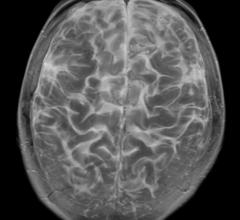

Neuro Imaging

Neuro imaging produces images of the structure or activity of the nervous system, usually the brain. It uses techniques like magnetic resonance imaging (MRI) and computerized tomography (CT).